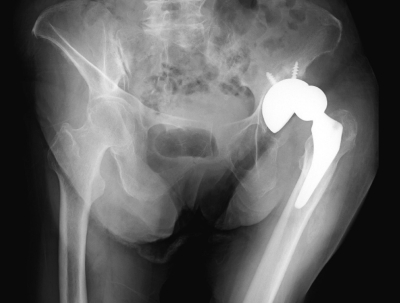

8か月前に左変形性股関節症に対する左人工股関節全置換術を受け、術後経過は良好で、股関節に痛みを感じることなく歩行できていた。既往歴に特記すべきことはない。左股関節は屈曲、内転、内旋位をとっている。血液生化学所見に異常を認めない。股関節のエックス線写真を示す。

初期対応として適切なのはどれか。